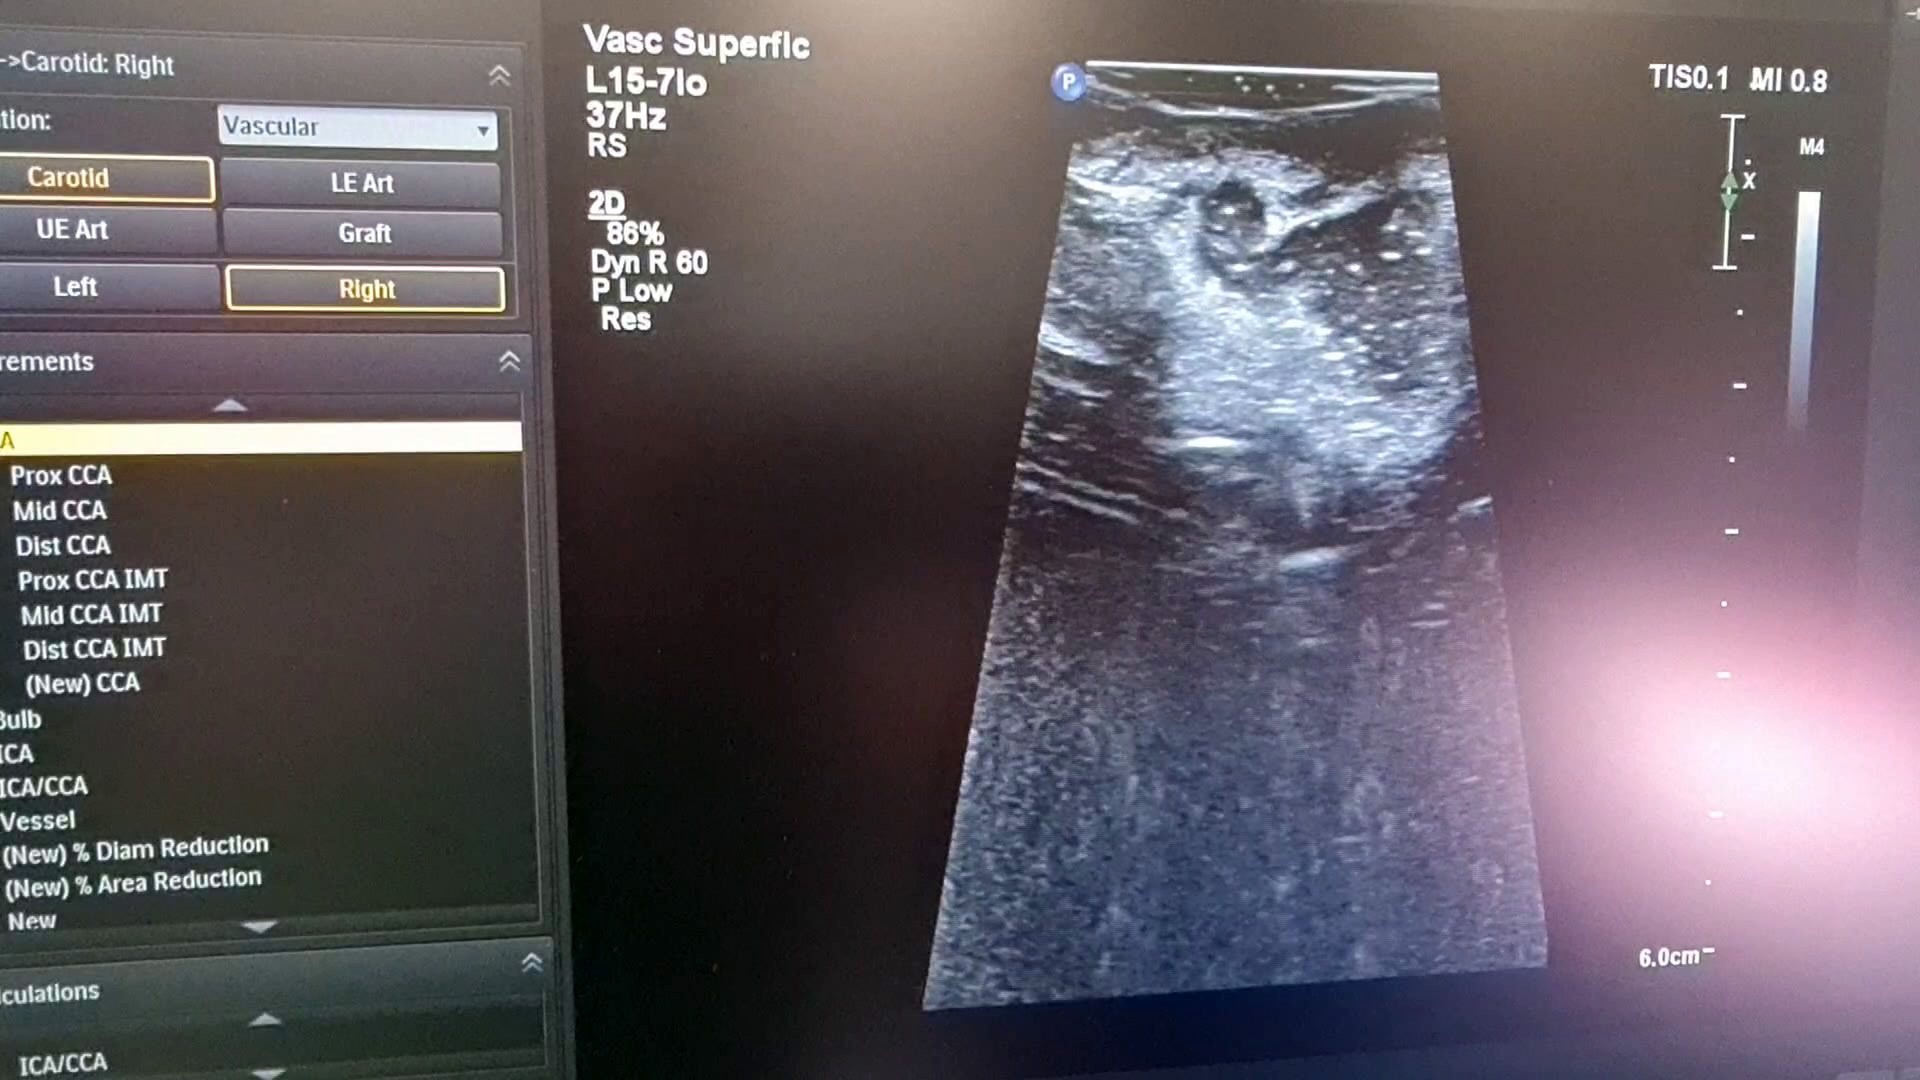

Ameliyathane de ilk ameliyat 27 yaşında beyninde tümör olan bir hastaya gerçekleştirildi. Uzun bir ameliyatın ardından hastanın ameliyatının tamamlandığı düşünüldü. Ancak ameliyatı gerçekleştiren Doç. Dr. Ömür Günaldı hastanın MR’ının çekilmesini istedi. Çekilen MR’da gözle ve ultrasonla görülmesi imkansız olan küçük bir tümör dokusunun kaldığı fark edildi. Hasta tekrar ameliyathaneye alındı ve ameliyata devam edilerek hasta da bulunan son parça da alınarak hastanın ameliyatı tamamlandı.

Bu yöntem ile yapılan ameliyatların çok daha güvenli bir cerrahi sağladığını belirten Beyin Cerrahi Kliniği İdari Sorumlusu Doç. Dr. Ömür Günaldı, “İntraoperatif MR da ilk beyin ameliyatımızı gerçekleştirdik. Önce ultrasonla görüntüledik daha sonra İntraoperatif MR çektirdik. Bu yöntem hasta için daha güvenli bir cerrahi sağlıyor. Bize de ameliyat esnasında sonucu değerlendirme imkanı tanımış oluyor” dedi.